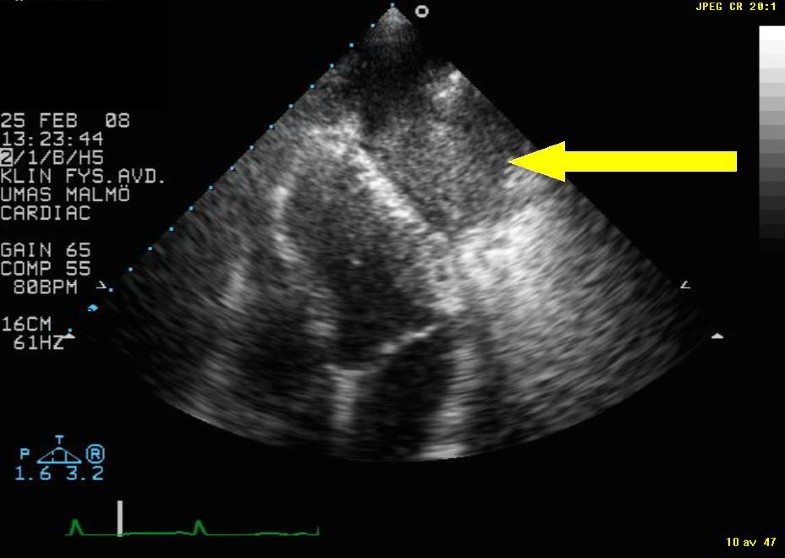

Primary Lung Tumour Visualised By Transthoracic Echocardiography

Primary lung tumour visualised by transthoracic echocardiography cardiovascularultrasound.biomedcentral.com

lung visualised tumour transthoracic echocardiography